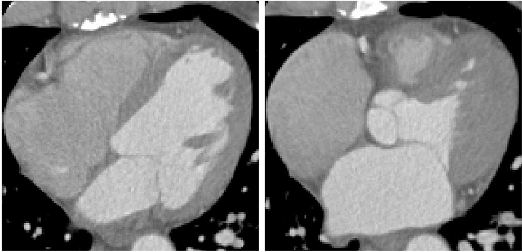

Refer to caption

(a) 4D-C-CT.

(b) 4D-L-CT.

Figure 7: A snapshot of the selected data at two time-points with the largest motion difference: (a) is the 4D-C-CT (axial views) showing the cardiac phases in the end-diastole (ED) and end-systole (ES), respectively of left and right; (b) is the 4D-L-CT (sagittal views) depicting the lungs in the states of maximum breath holding and minimum exhalation. The red line and yellow lines highlight the volume changes of the lung between two phases. (c) is the ACDC depicting the cardiac MR images in the ED and ES, respectively of left and right.

IV-A1 4D-C-CT

Fig. 7(a) shows a snapshot of randomly sampled cardiac volume slices from a sequence. The 4D-C-CT dataset consists of 18 subjects, each having 5 time-points (image volumes) capturing half cardiac cycle from ED to ES. Since the dataset contains several patients with left ventricular aneurysm resulting in abnormally subtle deformation, we select 12 patient data with large volume changes (volume changing rate from 0.37 to 0.75), and only test on these selected challenging datasets. Each volume is characterized by a high intra-slice (x- and y-) resolution ranging from 0.32 to 0.45mm and inter-slice (z-) resolution from 0.37 to 0.82mm.